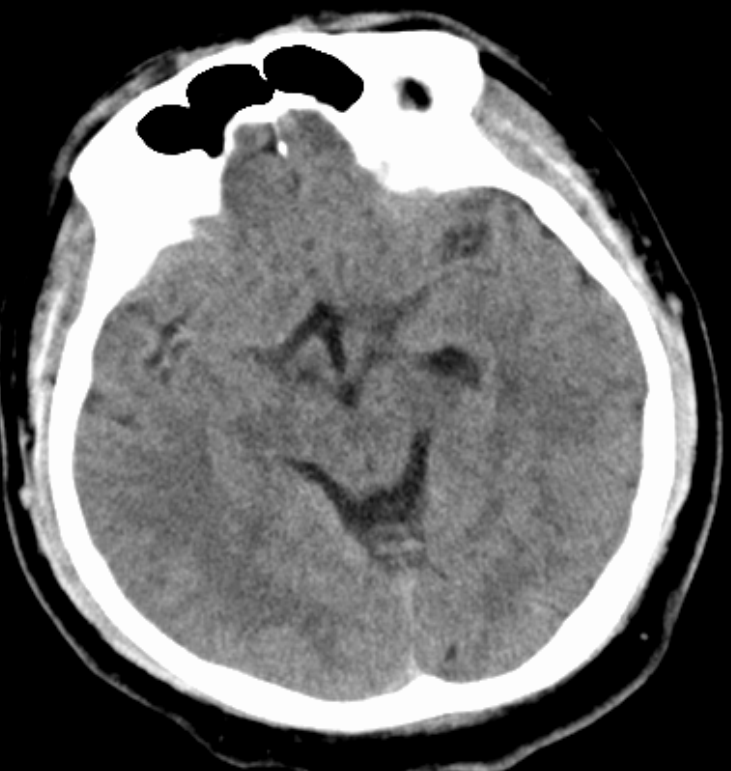

经急诊颅脑CT、核磁共振、头颈部CTA等检查,提示患者右侧大脑中动脉M1段闭塞。急诊医生紧急联系神经介入值班医生进行会诊。神经外科主任医师陈寒春结合检查结果,初步判断为急性脑梗死,立即启动脑卒中绿色通道。